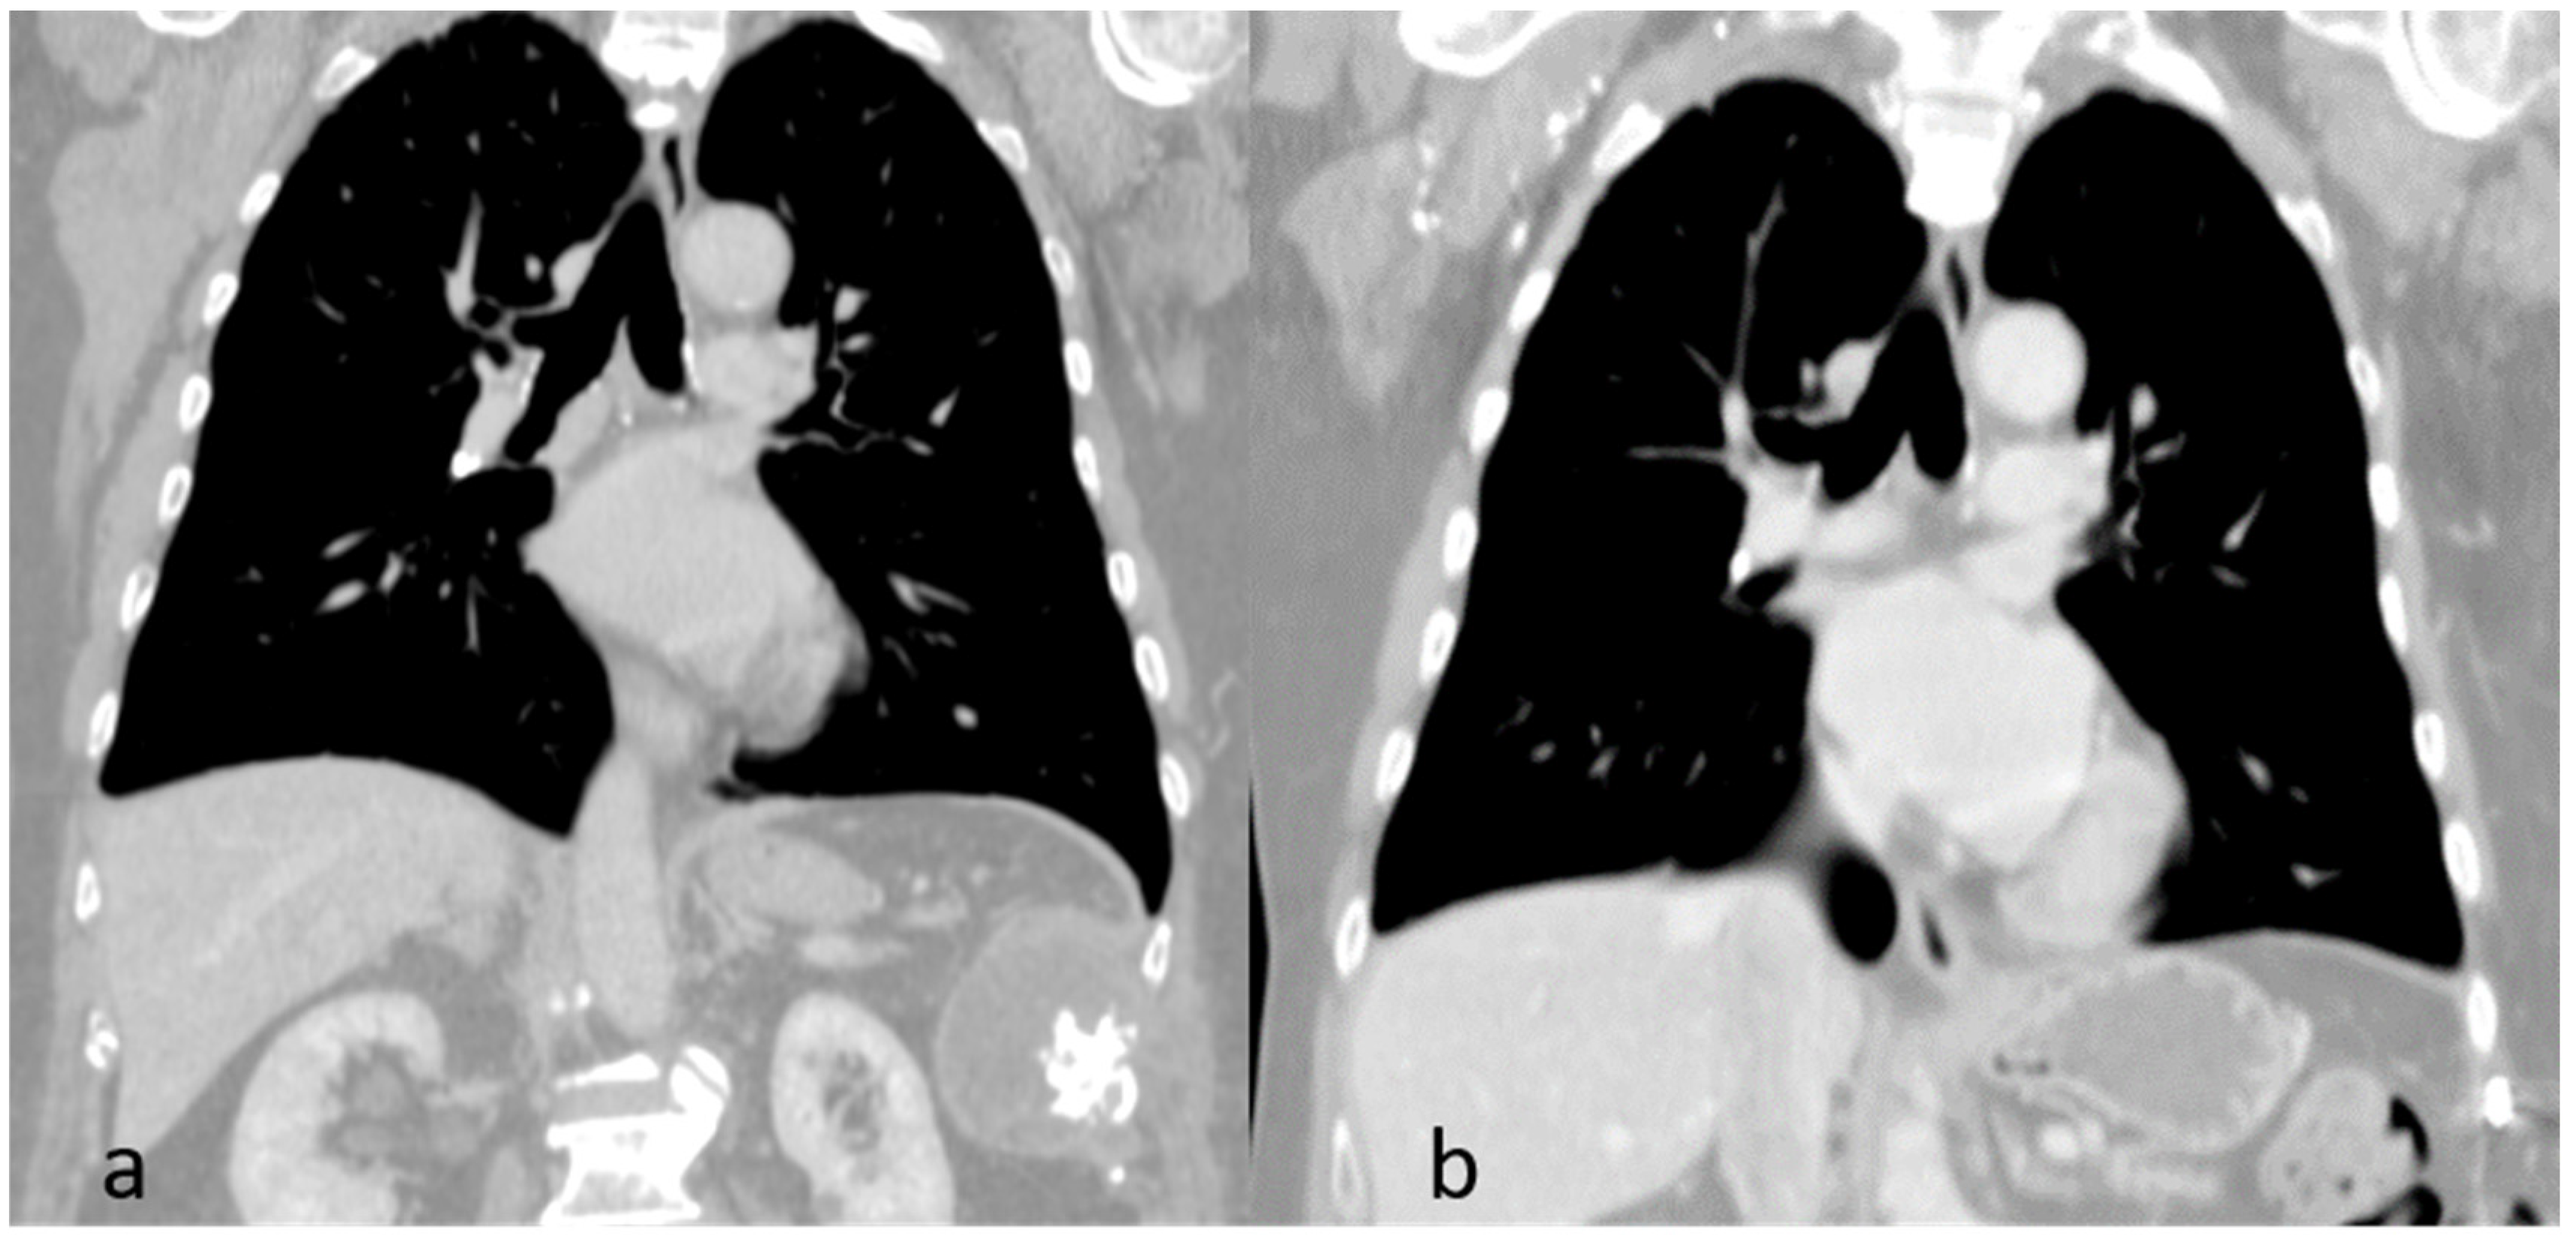

Figure 6.

Coronal view computed tomography scans: Pre-operative finding (a). Post-operative finding (b).